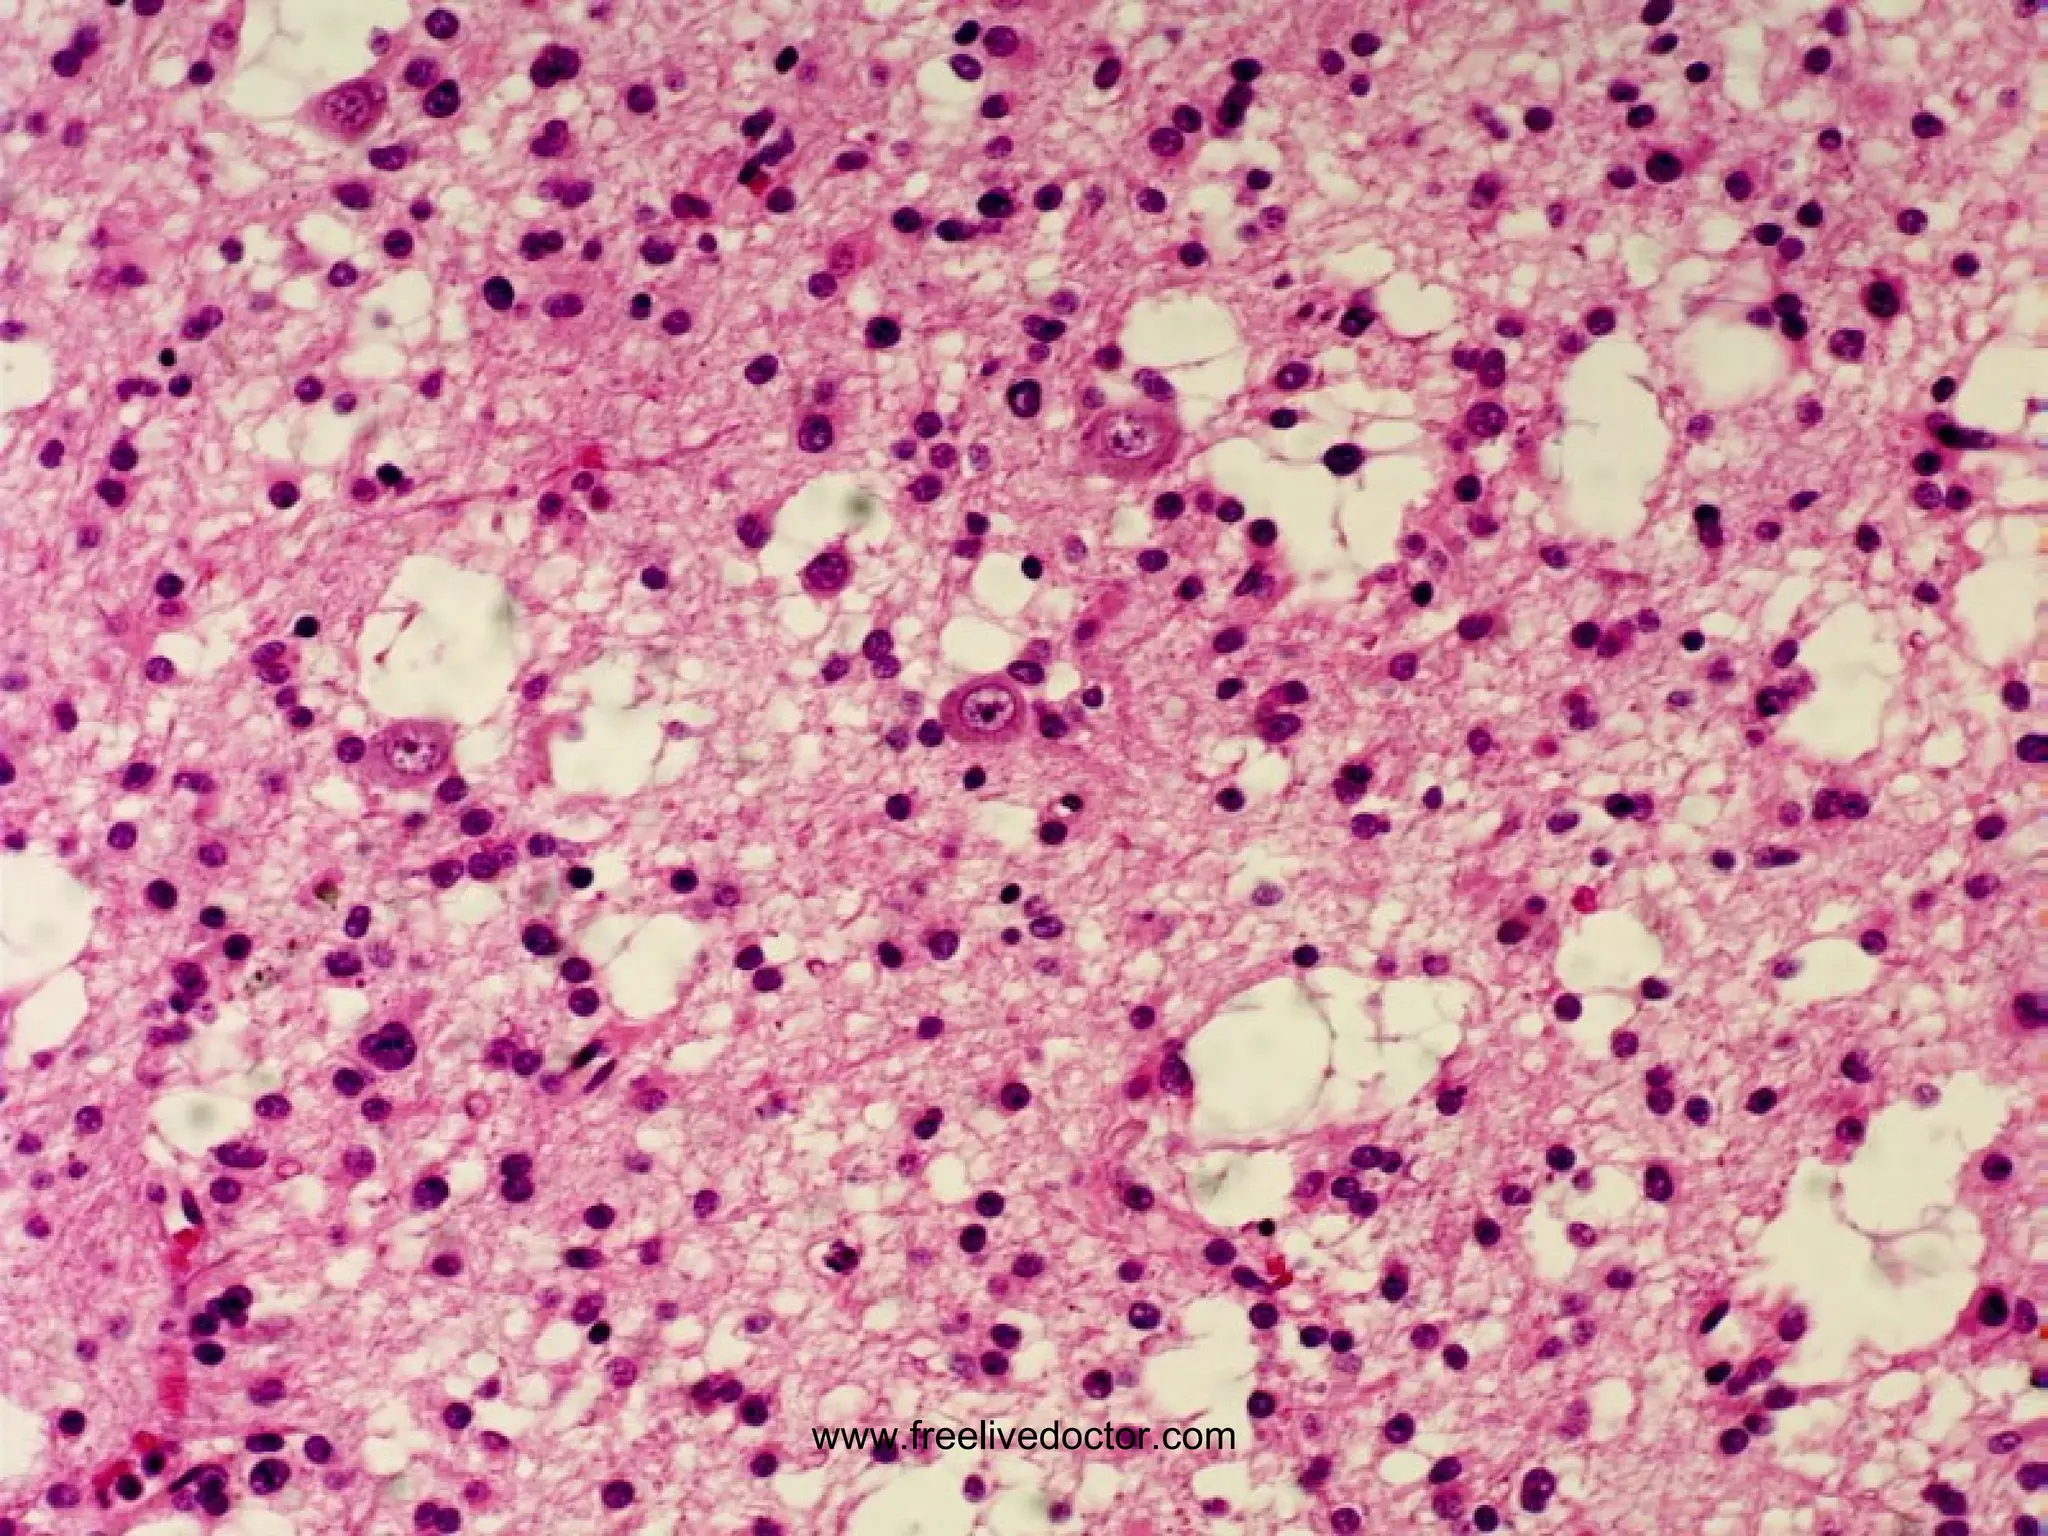

CRYPTOCOCCUS MICROABSCESSES www.freelivedoctor.com

FUNGAL MENINGO-ENCEPHALITIS CRYPTOCOCCUS CANDIDA ASPERGILLIS MUCOR (Mostly in immunocompromised hosts) www.freelivedoctor.com

OTHERS MALARIA TOXOPLASMOSIS (in HIV) AMEBIASIS TRYPANOSOMES RICKETTSIAE ECHINOCOCCUS www.freelivedoctor.com